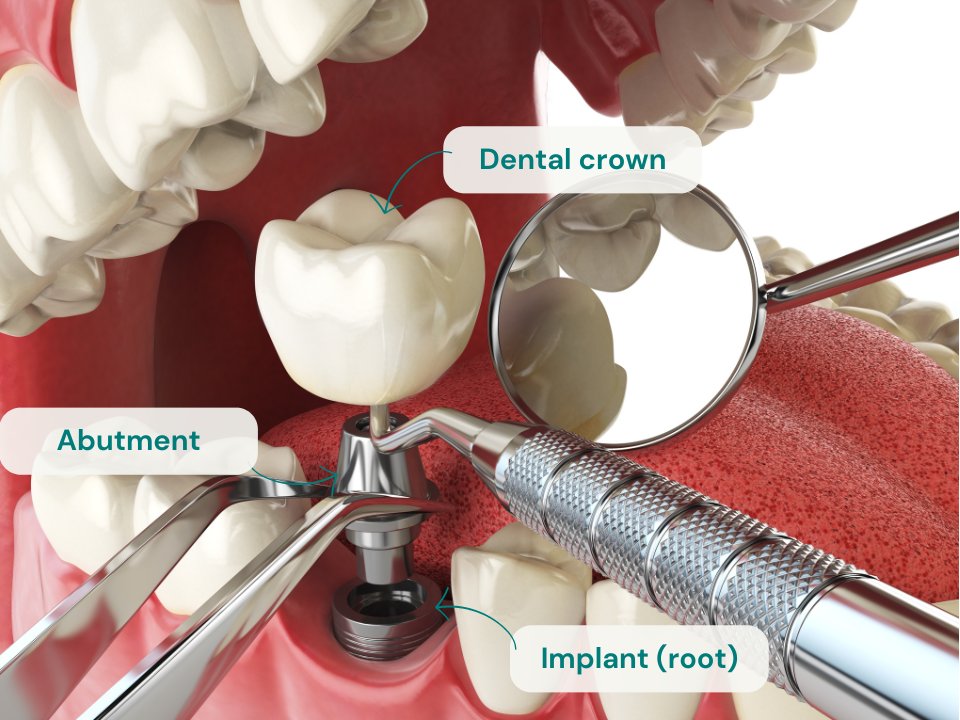

Un impianto dentale è una radice artificiale, realizzata in titanio o ceramica di zirconio, che funge da base per il nuovo dente artificiale.

Sopra questa radice artificiale (l’impianto) si monta la corona del dente artificiale. Il risultato finale è un dente completamente artificiale che comprende:

Impianto dentale

Perno o connettore

Perno o connettore, la parte che unisce l’impianto dentale alla corona

Corona dentale

Corona dentale, fatta di metallo-ceramica o ceramica pura senza metallo